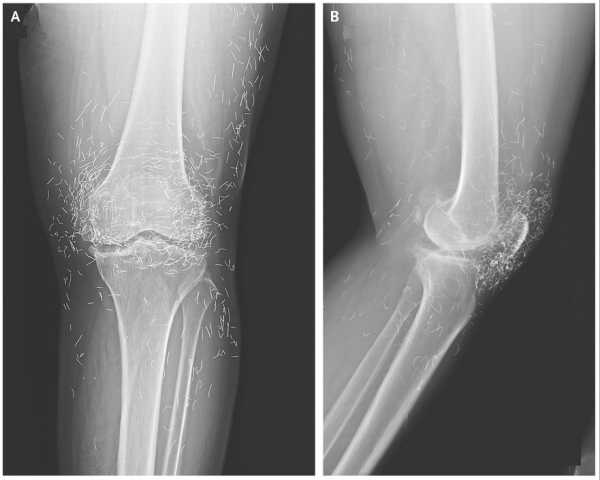

Сильний біль у коліні жінки виявив «золоті нитки» в її суглобах

Чоловік загалом був стабільним, але медичний огляд показав помітні зміни в м’язах плеча та грудей, що відповідали порушенням, виявленим на сканах. Потім лікарі переглянули історію хвороби пацієнта, і він поділився важливою деталлю: приблизно 30 років тому він почав отримувати «невідомі внутрішньом’язові ін’єкції (ймовірно, що містять тестостерон)» у м’язи грудей та плечей для їх збільшення, згідно зі звітом про його випадок.

Діагноз: під мікроскопом м'яз був заповнений силіконополімерною речовиною на масляній основі та оточений щільними кальцієвими відкладеннями. Команда вчених дійшла висновку, що попередні ін'єкції чоловіка в м'язи, ймовірно, містили синтол, речовину, що складається переважно з олії, яка візуально «наповнює» м'язи, по суті, надуваючи їх, як водяні кульки.

У цьому випадку синтол викликав стійку реакцію на чужорідне тіло — організм, по суті, реагував на матеріал, який він не міг розщепити. З часом ця реакція призвела до рубцювання та кальцифікації, що призвело до накопичення великої кількості кальцію всередині м'яза. І зрештою цей кальцій потрапив у його кров.